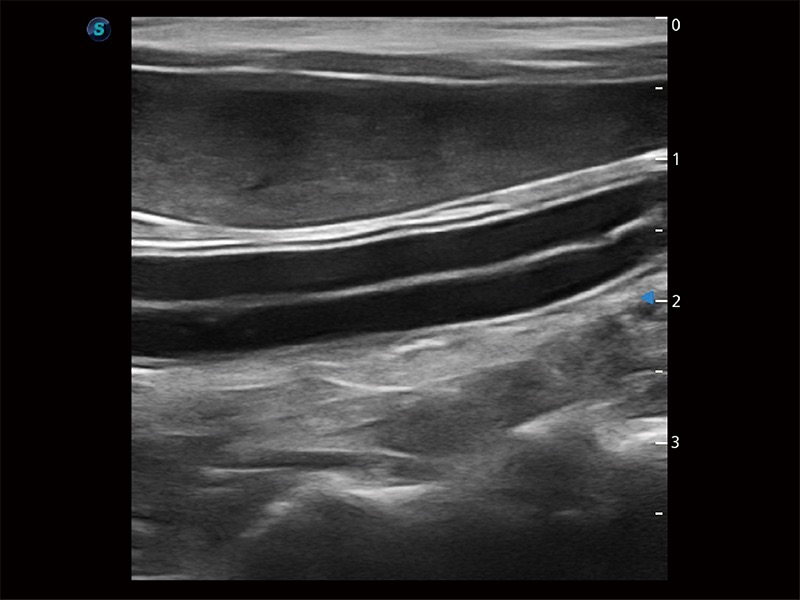

(犬)肠道

优异的基础图像

ProPet 80 全新的动物超声智能软件和丰富的探头群,为动物医生提供了高清晰度和精细分辨率的图像,无论在宠物、马科、畜牧还是实验室动物等应用中都可以轻松应对,为您的日常工作带来满意的体验。